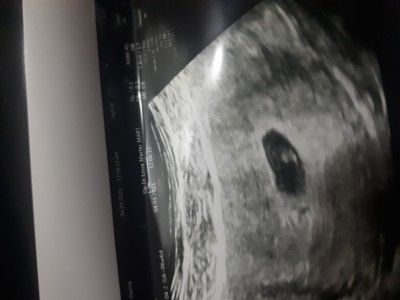

sizce bebek varmi gelisir mi

Doktorda emin degil bebek gozukmuyor 4-5 haftalik olabilir dedi kese ve yol ksesi varmis onun altinda tomurcuk gibi bisey varmis bebek olabilirms ama gelismemis birde rahim kalp seklindeymis . Belki buna benzeyen durum yasayan vardir anlar dedim . Birdahaki hafta belli olcak ama stres yaptm

Yolk kesesi varsa bebiste var oluyor diye biliyorum ben canım yolk kesesi bebeği beslemek.icin oluşuyor olmadığında boş kese oluyor senin attigin resimde bebiş var gördüm ben ama bence sen bi doktora da git tek doktorla yetinme

Boş kese görünüyor sadece ama doktor ne derse desin biraz bekle Allah gönlüne göre versin inşallah vardır

canim bak benim böyleydi kesenin içinde nokta gibi bişe var doktor onu göstererek bana bu yolk kesesi bu varsa bebekte oluşur demişti.

Senin kesenin içinde de bişe var görünüyor evet. Strest yapma inşallaah sağlıklı ilerler